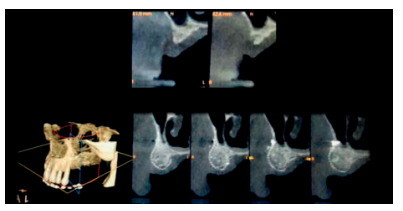

La regeneración localizada de grandes defectos horizontales en los procesos alveolares, previa a la inserción de implantes dentales, sigue siendo un procedimiento quirúrgico desafiante en cirugía bucal. Entre los procedimientos quirúrgicos más utilizados para tal propósito se encuentran la corticotomía con expansión, injerto en bloque “onlay” y la regeneración ósea guiada (ROG), todos ellos con sus diferentes grados de predictibilidad. El uso de micromalla de titanio en combinación con injertos y sustitutos óseos es un método eficiente para la contención, estabilización y protección de estos injertos, permitiendo así una mejor regeneración de los tejidos. Esta técnica no queda exenta de posibles complicaciones asociadas como pueden ser la infección, necrosis del injerto o exposición de la malla de titanio.

Localized regeneration of large horizontal defects in alveolar processes prior to the insertion of dental implants remains a challenging surgical procedure in oral surgery. Among the most widely used surgical procedures for this purpose are expansion corticotomy, onlay block graft and guided bone regeneration all of them with their different degrees of predictability. The use of titanium micromesh in combination with bone grafts and bone substitutes is an efficient method for the containtment, stabilization and protection of these grafts, thus allowing better tissue regeneration. This technique is not exempt from associated complications such as infection, graft necrosis or exposure of the titanium micromesh.

En regeneración ósea, llevada a cabo antes o durante la colocación de implantes dentales, los injertos de tejido duro (en bloque o particulado), tejido blando, así como la colocación de membranas barrera son considerados tratamientos quirúrgicos de elección por su elevada tasa de éxito (>95%)8 .

En los casos en los que se necesite un aumento óseo combinado en altura y anchura, las membranas no reabsorbibles fijadas con microtornillos serán el material más apropiado para una correcta fijación y estabilización del injerto. La complicación más común de las membranas no reabsorbibles es la exposición al medio bucal, que podrá generar infección y obligar la retirada prematura de la membrana provocando fracaso en el tratamiento3 .